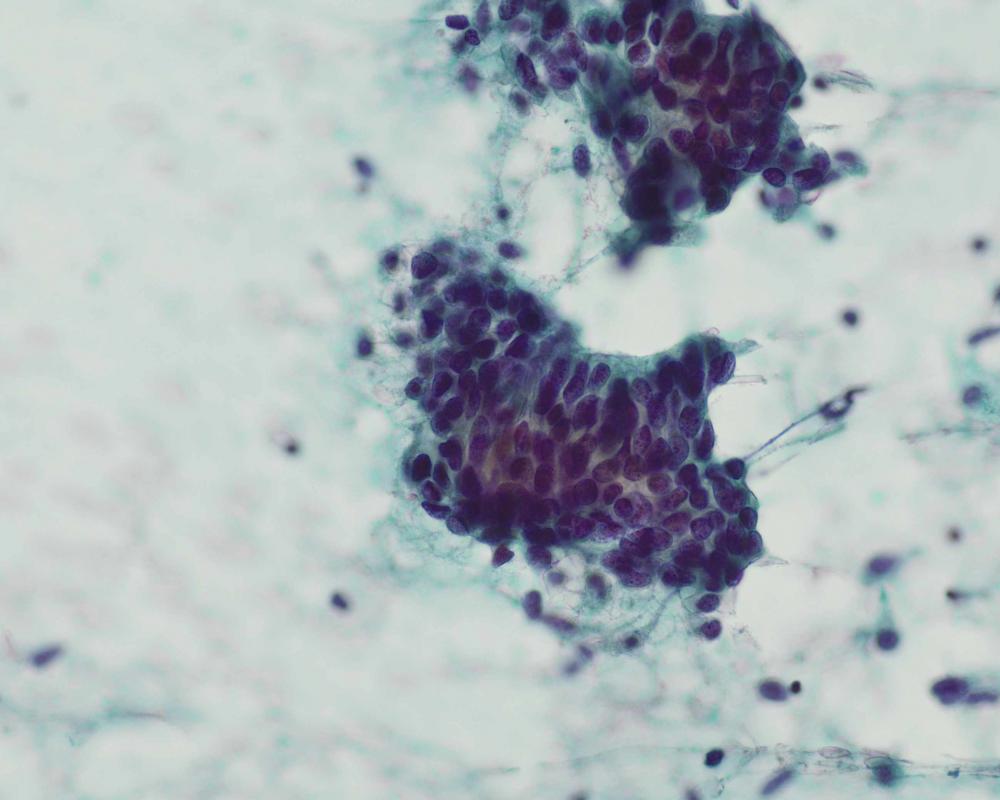

第37回日本臨床細胞学会九州連合会学会(佐賀)スライドカンファレンス症例3

出題:○山口 倫、阿部 英二.久留米大学医学部附属医療センター 病理診断科・臨床検査室

| 採取部位 | 右乳房C領域 | 採取方法 | FNA |

臨床所見

臨床診断:乳癌疑い

臨床経過:約2ヶ月前から、右乳房のしこりを自覚し来院。

触診上、右乳房C領域で、乳頭から約3cmの場所に、径1.5cm大の

硬い腫瘤を触知する。

| 正解 | 1.腺筋上皮腫 |